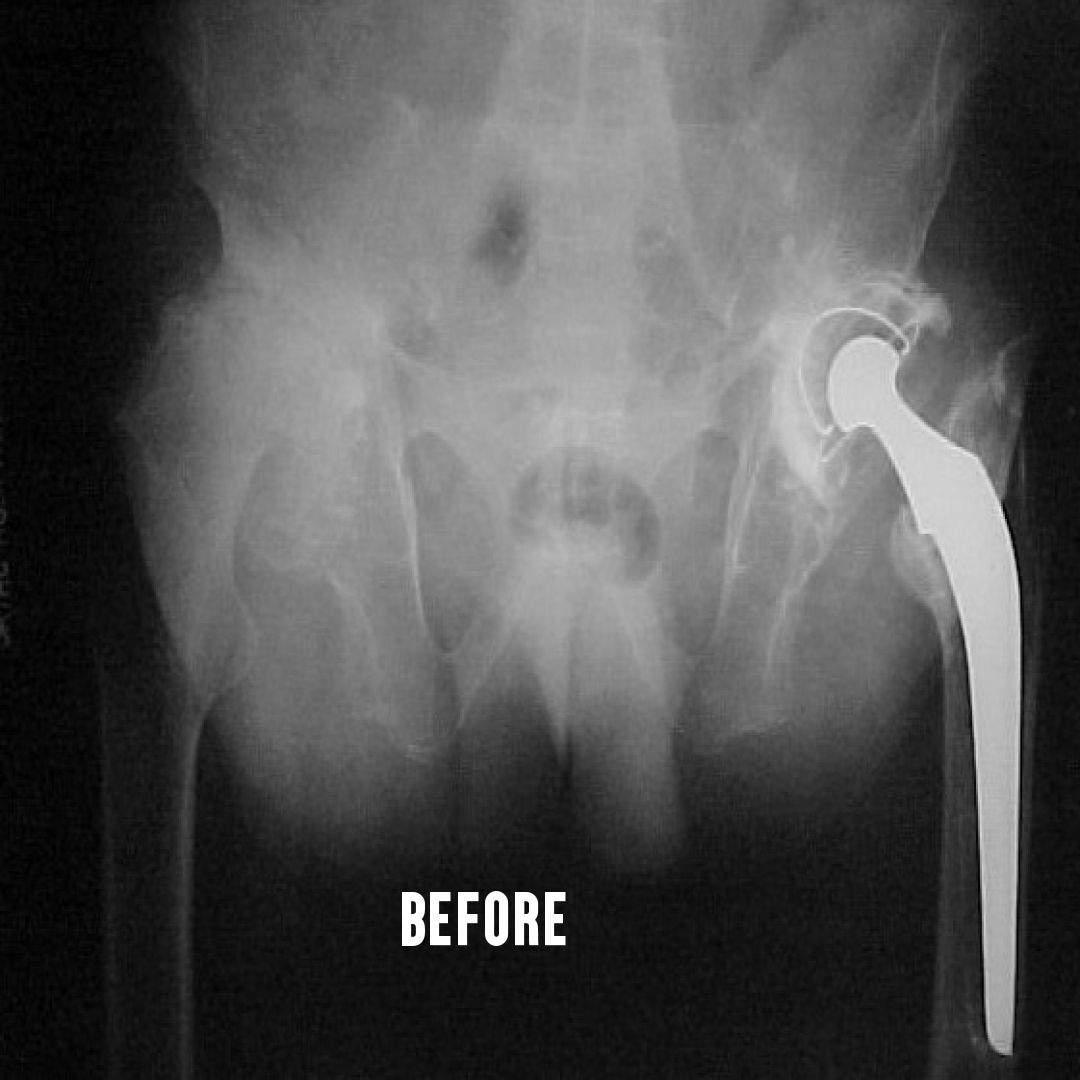

This is a surgery where both the ball and socket of the hip joint are replaced with artificial materials.

The normal hip joint consists of a cup called the acetabulum into which articulates a head of the thigh bone called the femur.

This joint may become damaged due to a variety of conditions. The common

causes are rheumatoid arthritis, ankylosing spondylitis, childhood diseases

like perches, injury to the hip joint etc. There is loss of articular cartilage, a

smooth lining of the ends of the bone in a joint. The result is that raw bones rub against each other causing pain. This condition where the articular

cartilage is damaged, is collectively called arthritis.

Damage to hip joint can occur at any age. Total hip replacement can be done

after the age of 20 years...Learn More